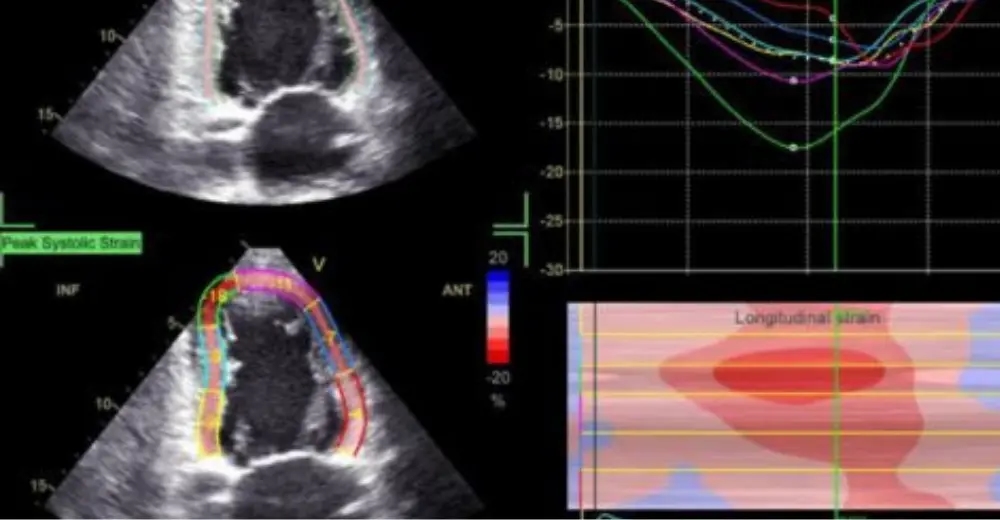

📈 Каким образом представляется результат?

Чаще всего оценивается глобальный продольный стрейн (GLS) левого желудочка. Математически обработанный результат представляется в виде 16- или 17-сегментной диаграммы (bull`s eye), графиков и значений GLS, полученных из трех различных срезов (LAX, A2Ch, A4 Ch) и среднее значение GLS